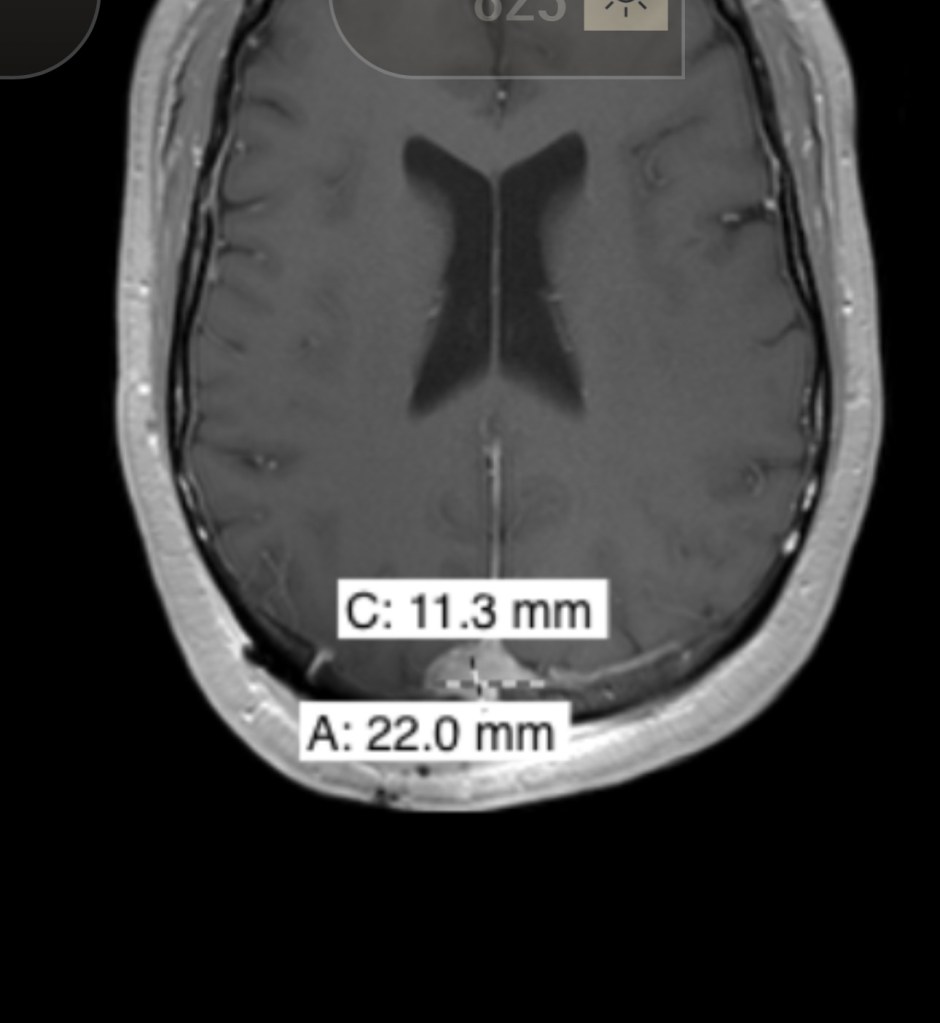

The MRI looked good. Since they couldn’t take out the whole tumor without cutting into that main blood vessel they showed how small his Neurosurgeon was able to get it which looks like it was 2.1cm X 0.9 cm. Beyond that, everything looks on track for a person who had surgery 24 hours ago.

To remind everyone about the size and location of the tumor